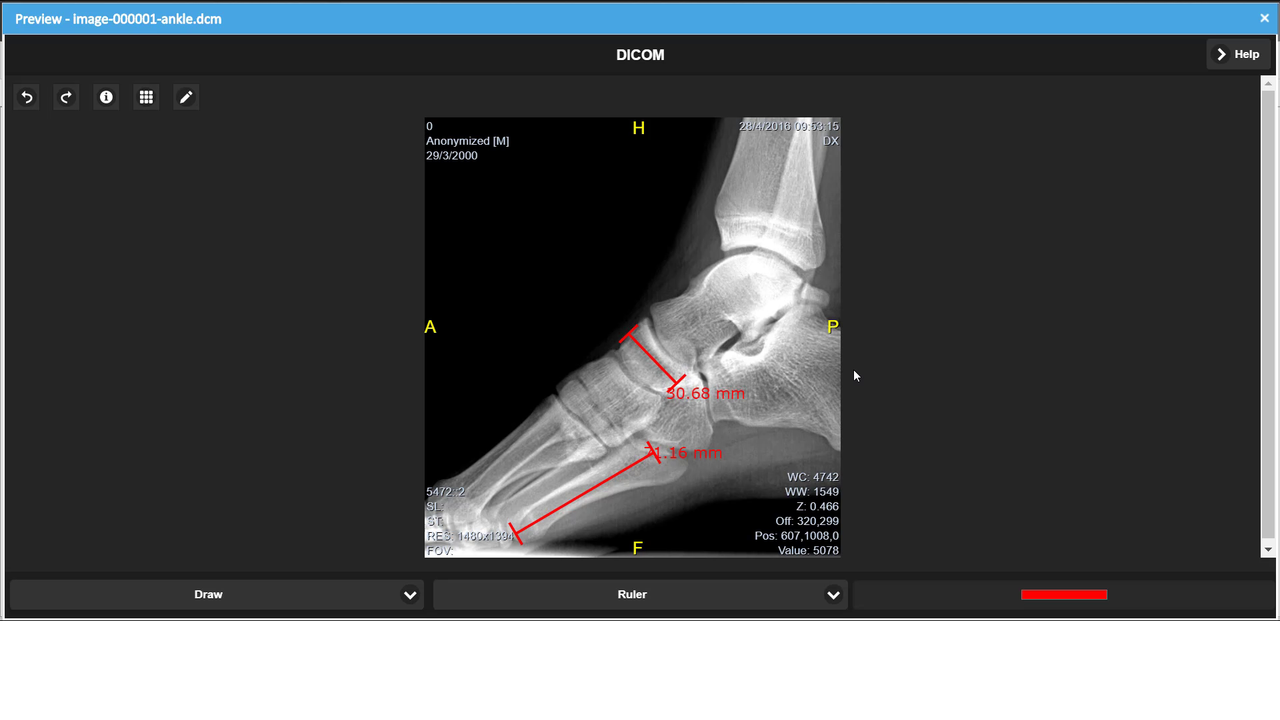

Ab LogicalDOC 8.3 ist die Vorschau von medizinischen Dokumenten im DICOM-Format verfügbar.

Einzelheiten der Funktion

- Werkzeuge zum Messen von Abständen, Winkeln und Flächen

Screenshots